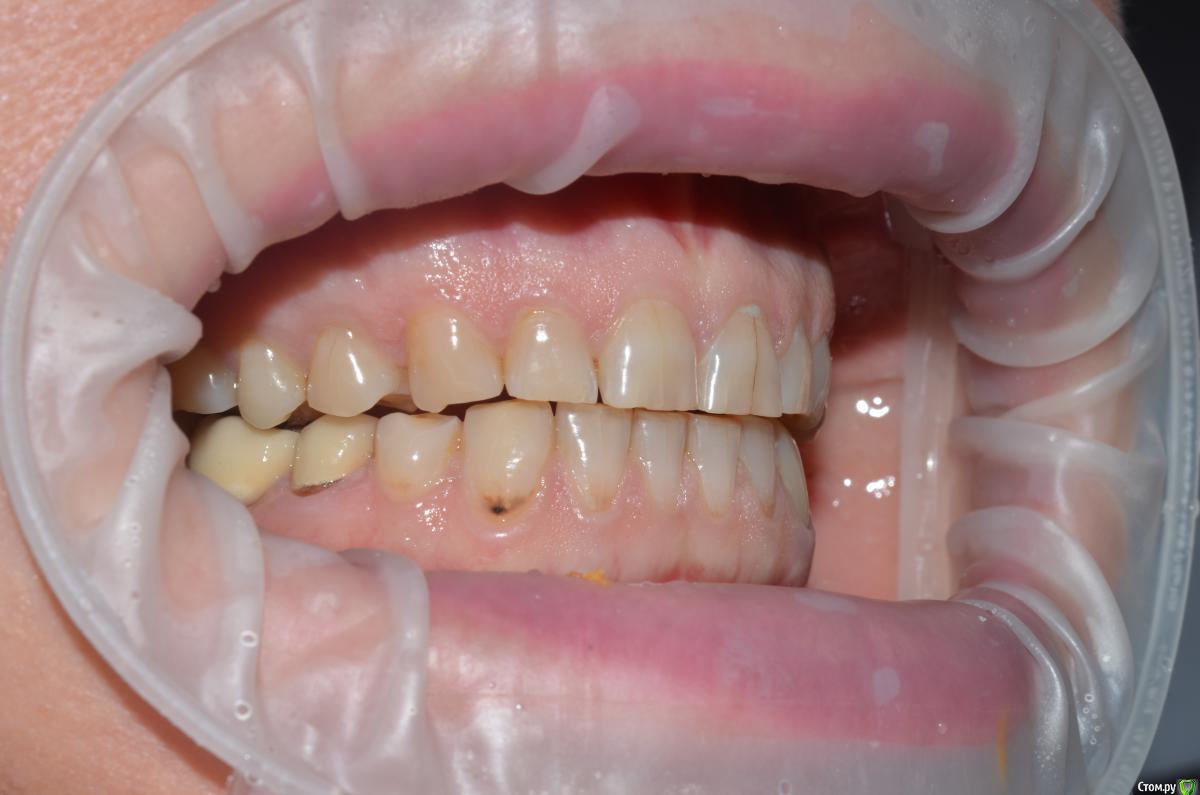

NazranDantist Опубликовано 4 сентября, 2015 Автор Поделиться Опубликовано 4 сентября, 2015 Продолжение кейса. Работа еще не закончена, зуб 25, 35, 36 - аббатменты на подходе, поэтому решили сделать после отпуска пациентки. Фото протокол не соблюдал, курс рубля прыгал, торопился в обменник . Вся работа - имакс на Цереке с редуцированием, фиксация - фронт на чойс, боковые - У-200. Ссылка на комментарий

Freelancer1981 Опубликовано 4 сентября, 2015 Поделиться Опубликовано 4 сентября, 2015 Как цс определяли?Я бы верхние режущий край у верхних зубов(отпрепарированных)загладил,а то разительный контраст с нижними..Фото бы день денька через 3-4.. Ссылка на комментарий

CHEREDNICHENCO Опубликовано 12 сентября, 2015 Поделиться Опубликовано 12 сентября, 2015 Режет глаз смещение цл, оптг необходимо определенно, хотя бы для оценки состояния тттз и периапикальных тканей в 4 секторе.... Индикатор кариеса используете в работе???.... А зачем в 3 секторе оставили временную конструкцию?! Или это постоянная???..... В десятых- эстетически не вяжется соотношение нижних к верхним... PS: В связи с определенным географическим положением, КНДР находиться в 1 км. 44 м. от места моей работы! и хочу сообщить Вам,- уровень их работ растет от из года, в год! Ссылка на комментарий

CHEREDNICHENCO Опубликовано 13 сентября, 2015 Поделиться Опубликовано 13 сентября, 2015 Кариеса нет.DSC_0643.JPGСмещение естьПо фото, когда зубные ряды находятся в контакте- смещение есть! Но на первых фото, когда НЧ находиться в состоянии относительного физиологического покоя, смещения нет! ТО делаю вывод, смещение возникает в результате неправильного соотношения жевательных поверхностей зубов. Ссылка на комментарий